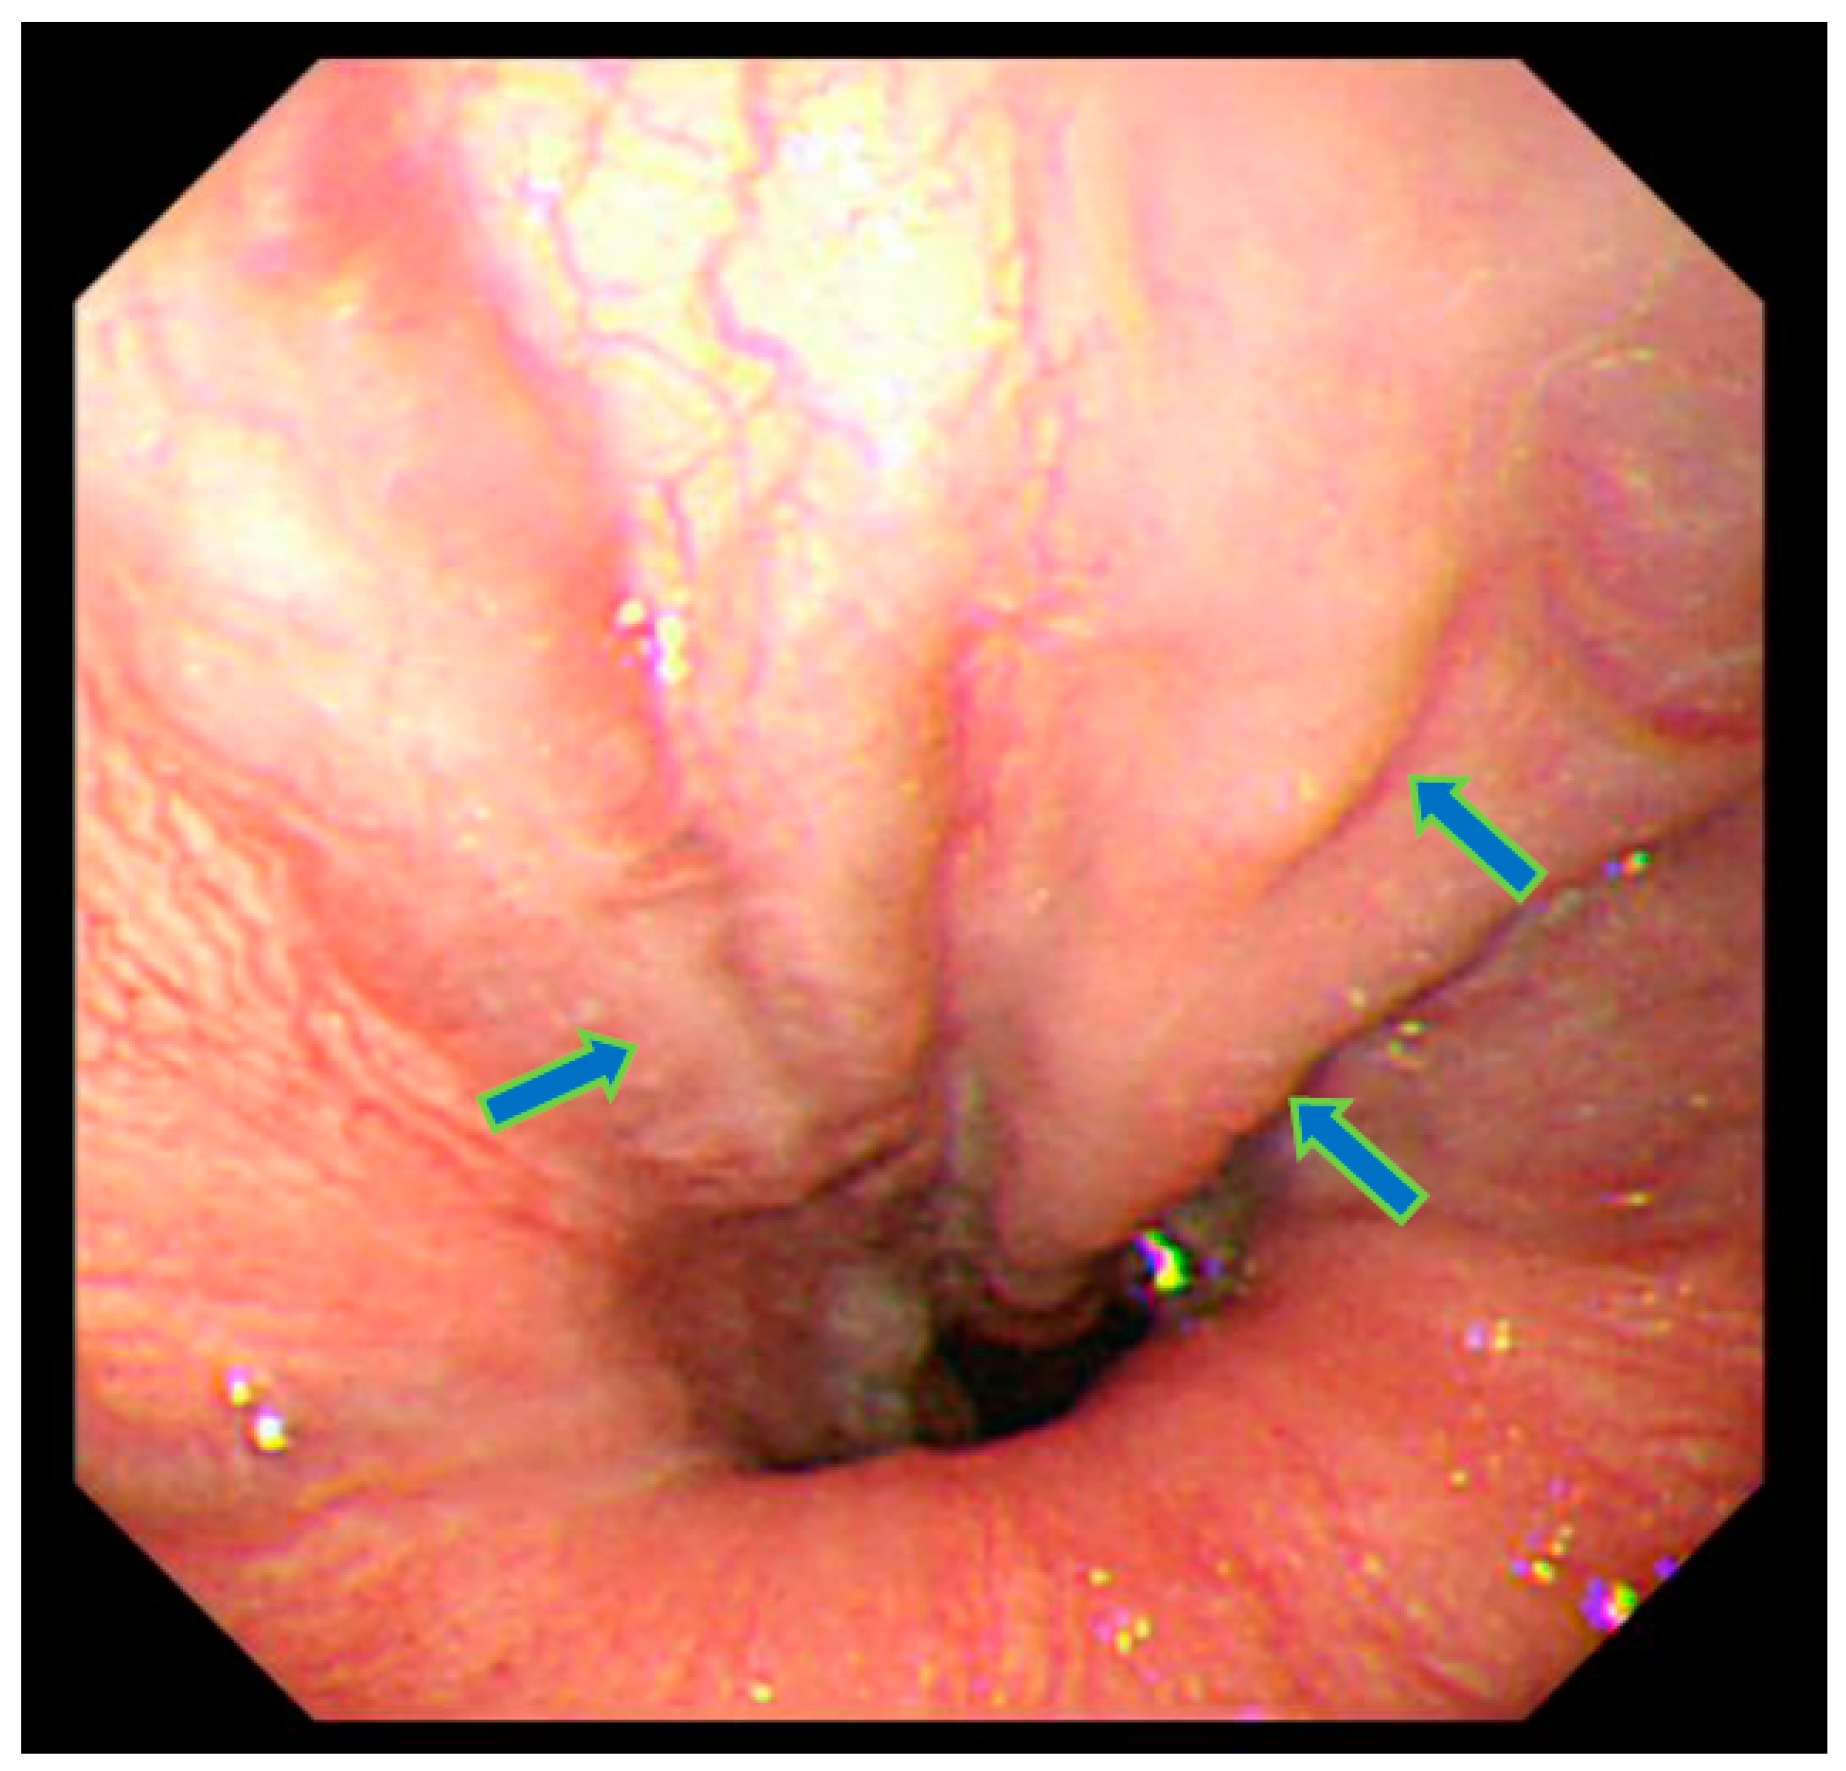

At age 47, the patient experienced stomach discomfort and underwent upper gastrointestinal endoscopy, which incidentally revealed esophageal varices (Figure 1). There was no relationship between the stomach discomfort and the esophageal varices. His height was 155.2 cm (−2.5 SD) and his weight 72.2 kg (body mass index: 29.9 kg/m2). The patient was not married and worked as a computer engineer. He had no family history of diabetes mellitus and no history of a drinking or smoking habit. In a physical examination, there were no cutaneous changes indicating extrahepatic manifestations of palmar erythema or spider angioma. Moreover, dilated superficial abdominal vein and hepatosple nomegaly were not observed at that time.

Figure 1.

Upper gastrointestinal endoscopy showing esophageal varices in the lower esophagus (arrows). Varicose veins have the same color as normal esophageal mucosa. Bleeding or redness on the surface was not recognized. Judged to be grade 1.